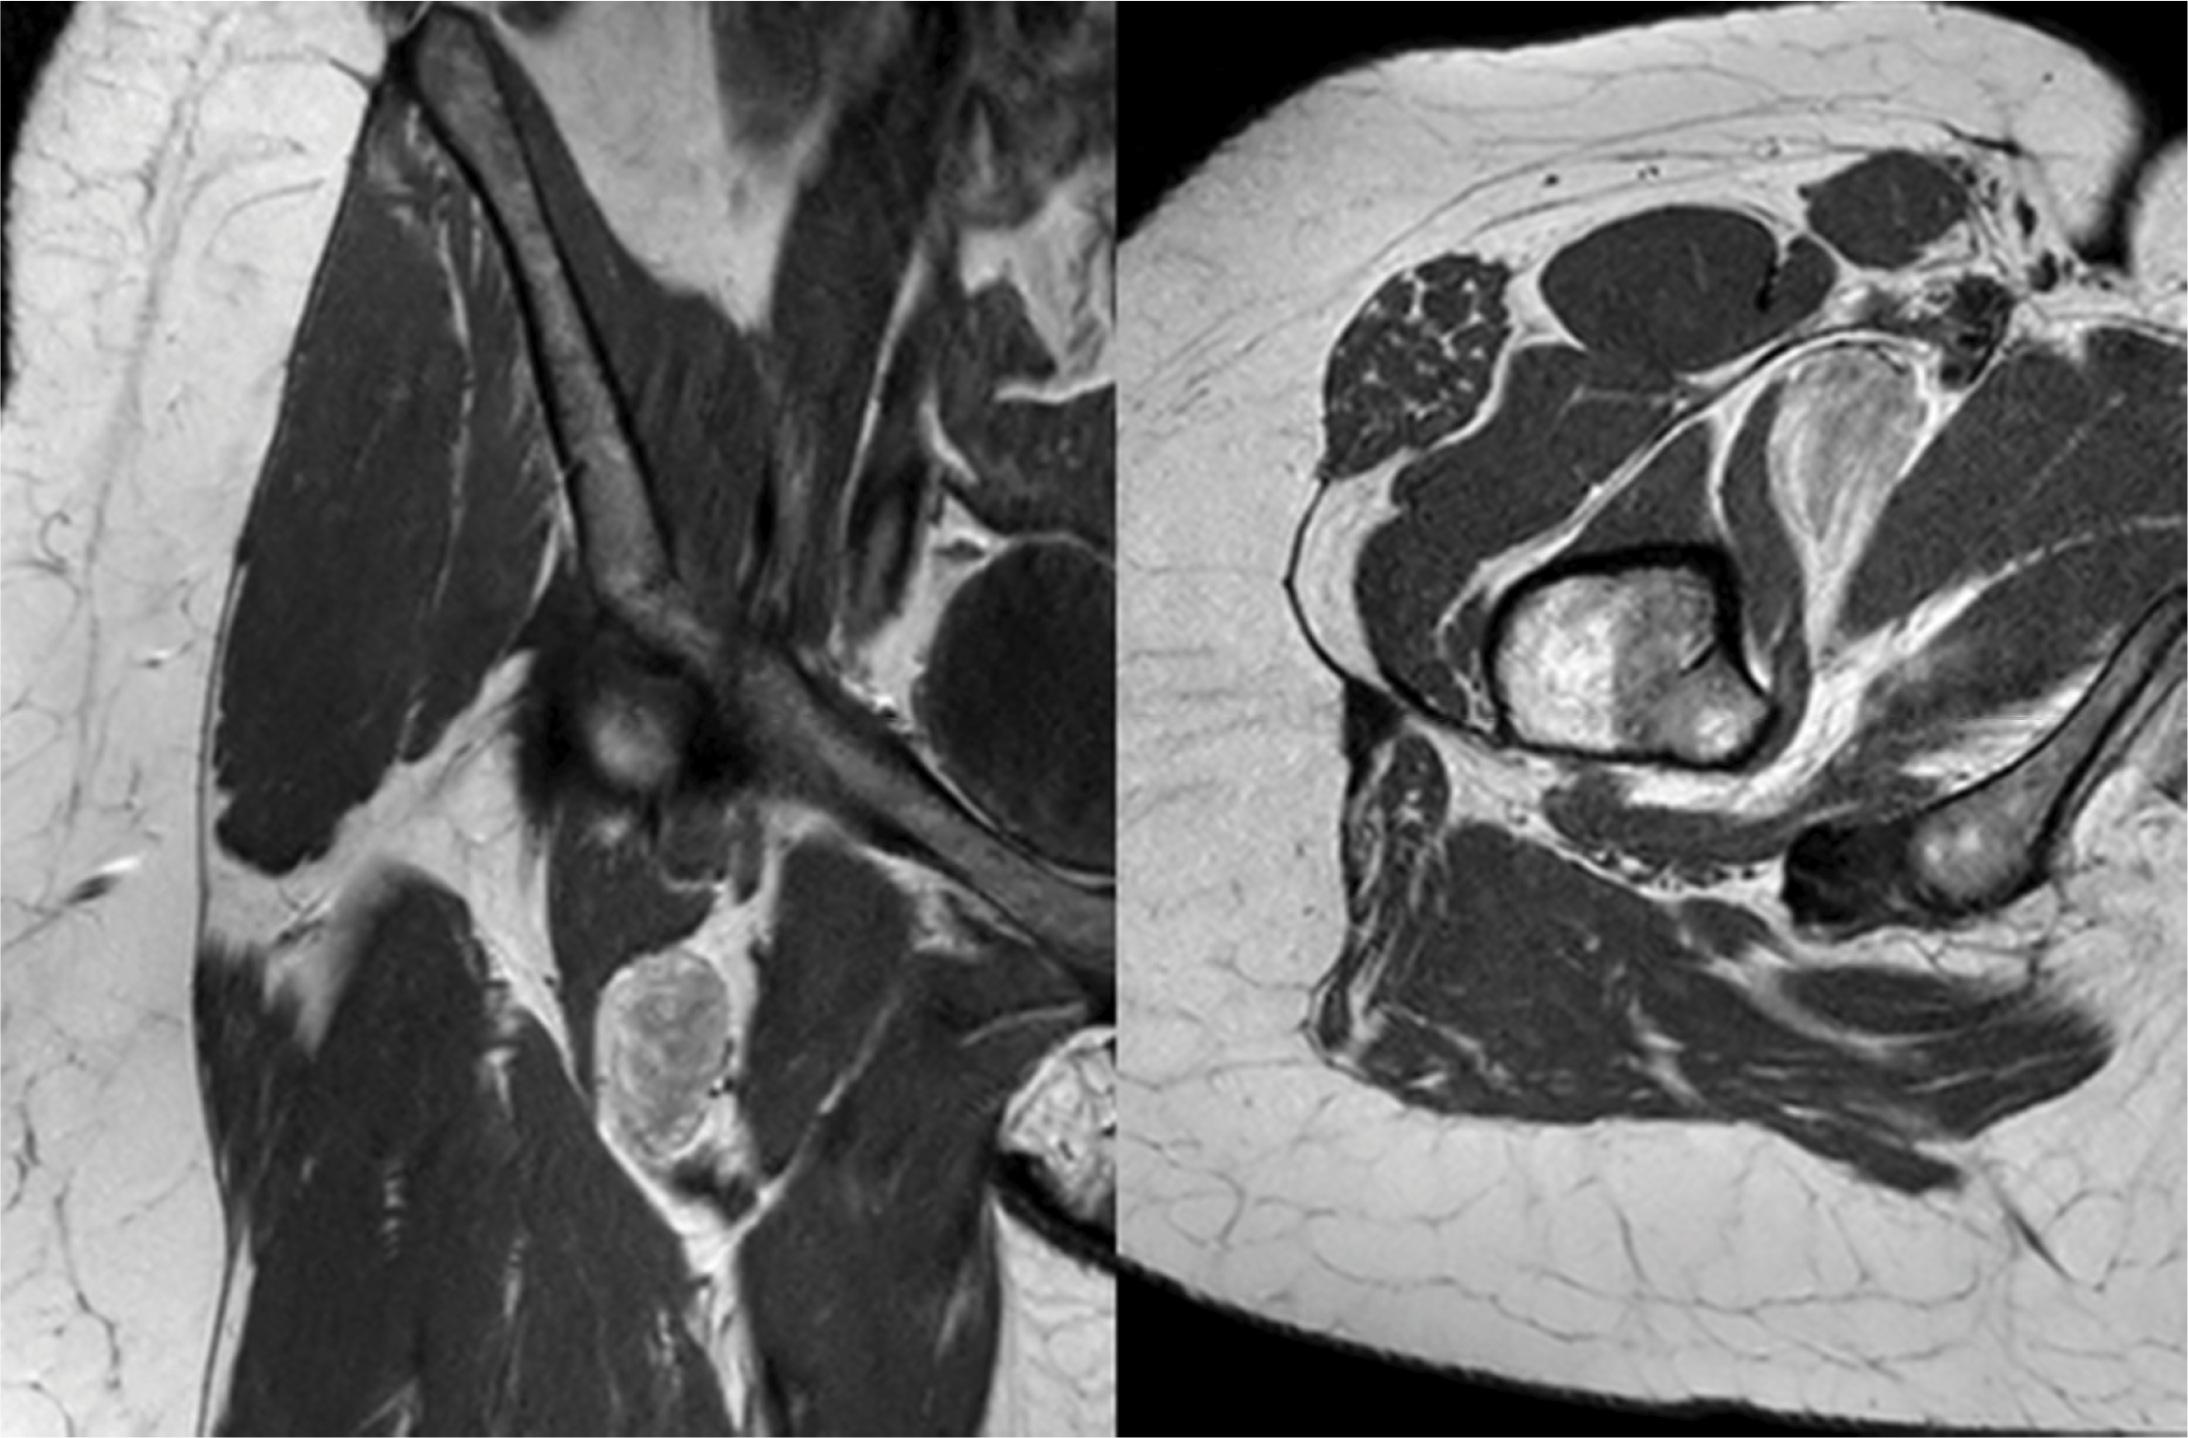

Figure 1

Coronal and axial T1 weighted MRI images revealed a well‑circumscribed mass in the deep right inguinal region with mixed signal intensities.